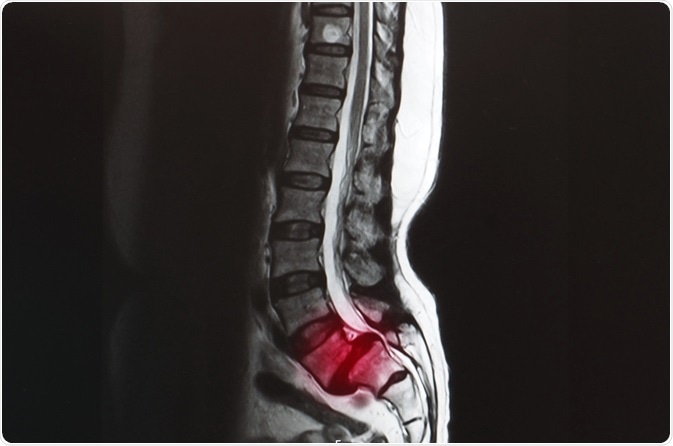

Spondylolisthesis. Image Credit: Yok_onepiece/Shutterstock.com

All patients with spondylolisthesis will experience changes in the positioning of the vertebrae of the spine, displaced forward. These changes may be accompanied by resulting symptoms, such as stiffening of the back and tightening of the hamstring muscles in the legs.